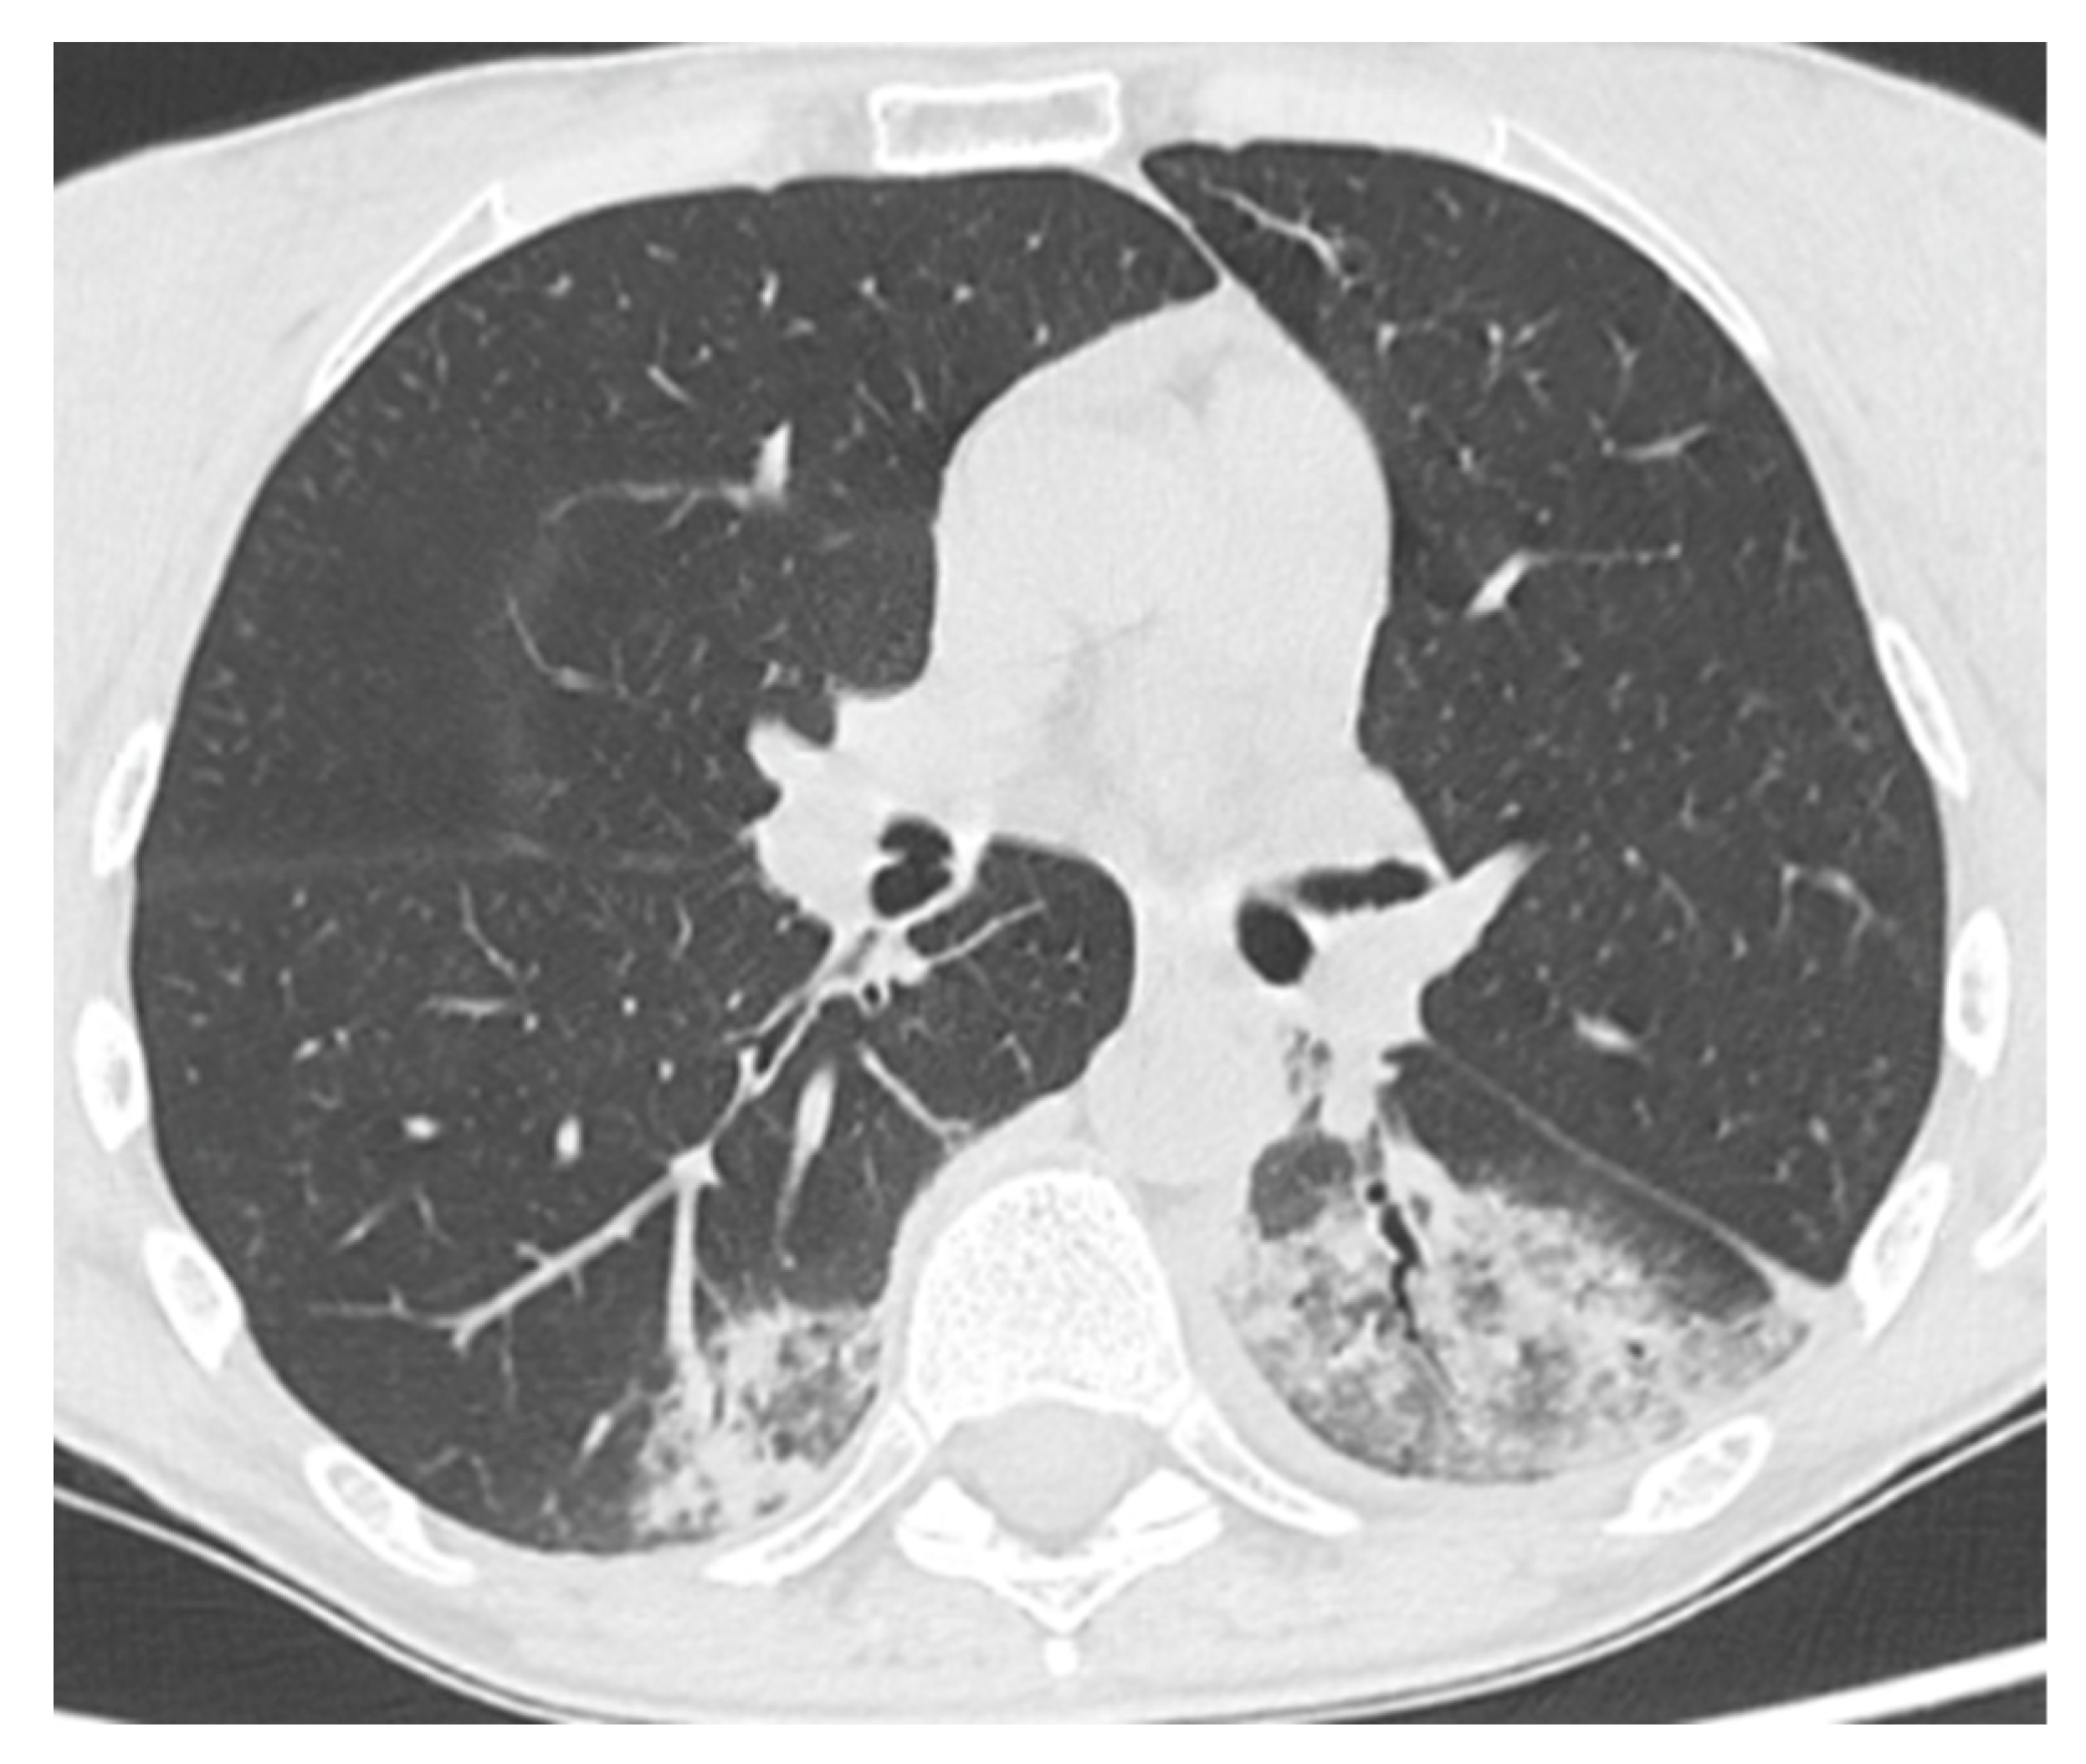

| Comorbidity | RA | Splenomegaly, bronchiectasis; recurrent viral infections | Hypertrophic cardiomyopathy; AF; CKD secondary to nephrolithiasis. C | Bronchiectasis; COPD; EBV-related NHL | GLILD; Bronchiectasis; colonization Aspergillus; Sjogren syndrome; CKD |

| SARS-CoV-2 related pneumonia | yes | yes | yes | yes | no |